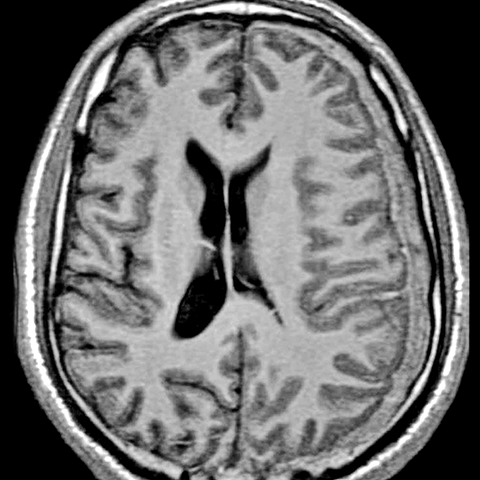

Subdural Hematoma [2 of 3]